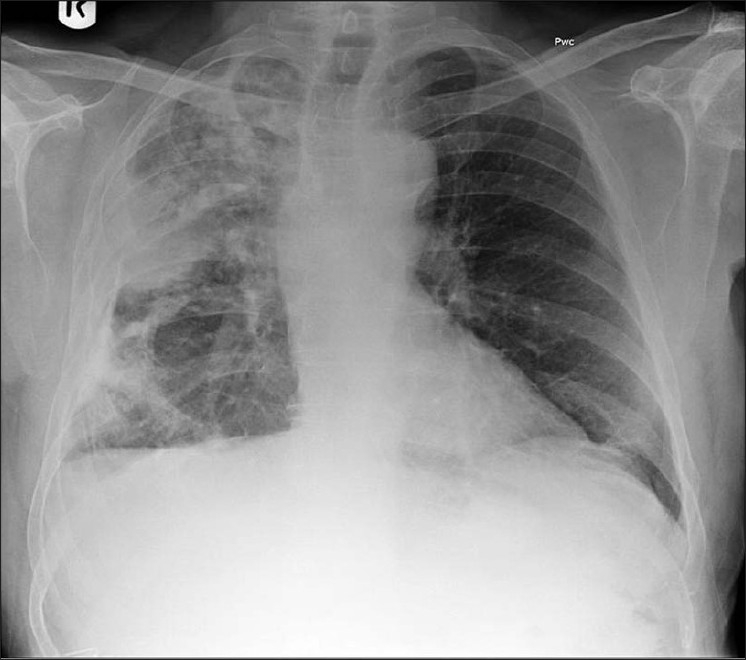

Mesothelioma Cancer Figures / Cancers | Free Full-Text | Chimeric Antigen Receptor (CAR. Mesothelioma is a rare cancer—2,875 cases were reported in the united states in 2018. Mesothelioma is fairly rare in the united states. Mesothelioma is a rare cancer. Learn more about this disease, including its associated symptoms and risk factors, here. Cancer incidence and mortality statistics worldwide and by region.